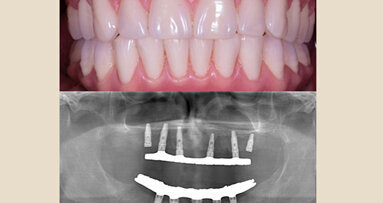

Una vez que el laboratorio procesa la prótesis, se cita al paciente para entregarle la prótesis. Se utiliza torque a 30 Ncm2 y se coloca SysTemp Onlay® (Ivoclar) para sellar los accesos oclusales.

Figs. 39 y 40. Prótesis híbrida final.

Fig. 41. Radiografía panorámica final.